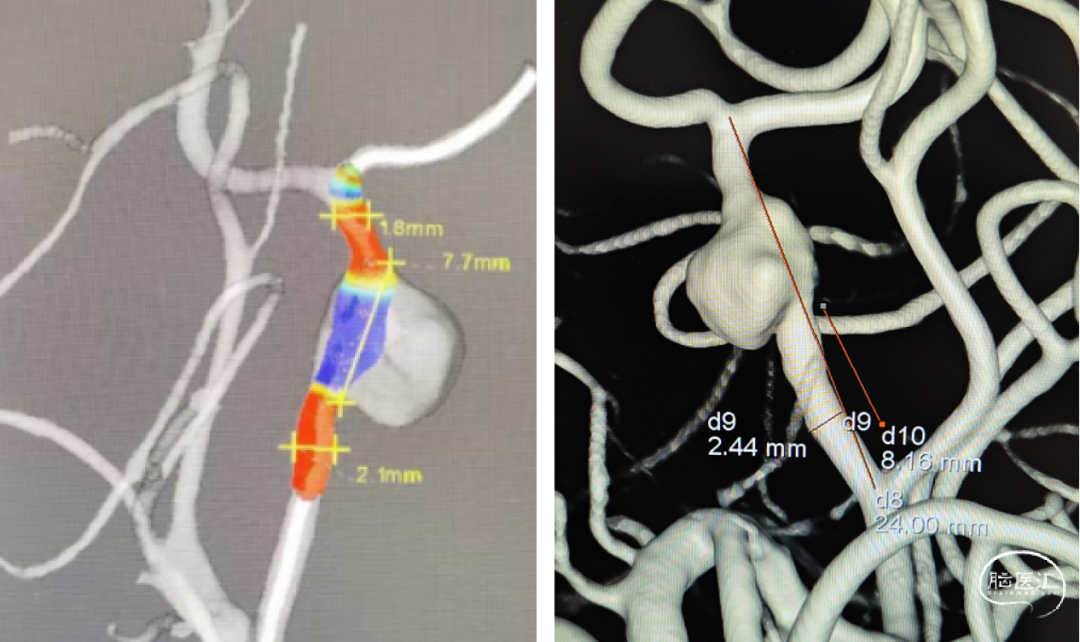

外院CTA:左侧大脑中动脉M1、M2段动脉瘤

AI风险评估

手术规划:FD+弹簧圈